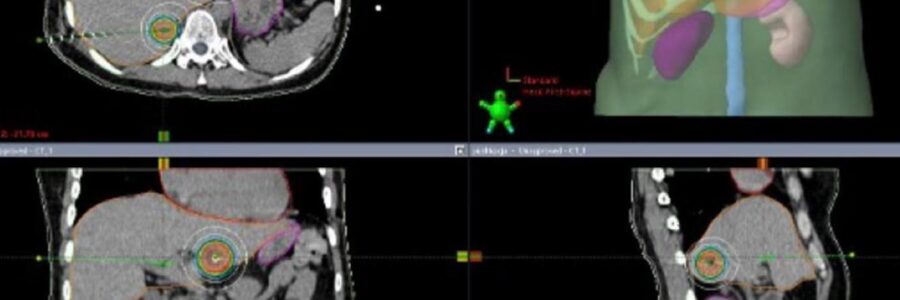

Read More Banery Brachyterapia HDR 7 września 202519 października 2025Administrator35 views Przeczytaj